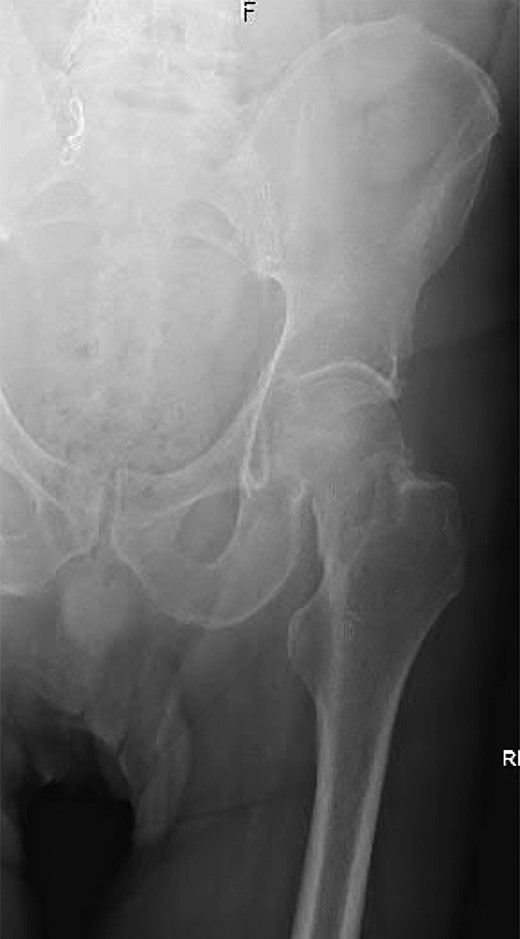

A 74-year-old male was admitted with an intracapsular fractured left neck of femur (Fig. 1). According to the NICE guidelines, he received a cemented THR (Fig. 2) via the posterior approach in the lateral decubitus position. Five weeks prior, he had an EVAR for a leaking AAA. Due to a calcified, narrow right common iliac artery (CIA), the EVAR consisted of a left aortouniiliac endograft with coil embolization of the right CIA and a femoro-femoral crossover graft (Figs 3 and 4).

Anteroposterior (AP) radiograph of the left hip demonstrating a complete and partially displaced, intracapsular fractured neck of femur.